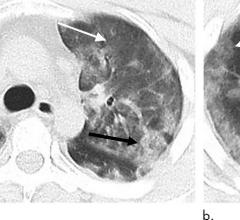

February 11, 2020 — The Radiological Society of North America (RSNA) journal Radiology has published a study from ...

February 4, 2020 — Since January 2020, the Coronavirus (2019-nCoV) outbreak at Wuhan, China, has attracted a great deal ...